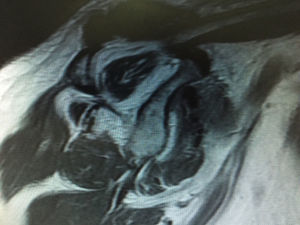

Clasificación de acuerdo con la calidad del tendónLa calidad del tendón se puede evaluar por TC o RM y su función principal es determinar si el tendón, por su calidad, es reparable. La clasificación más usada es la clasificación de Goutallier (tabla 5), basada en la existencia de infiltración grasa en imágenes de TC. Fuchs ha publicado también una clasificación similar con el uso de RM (figs. 3–6).